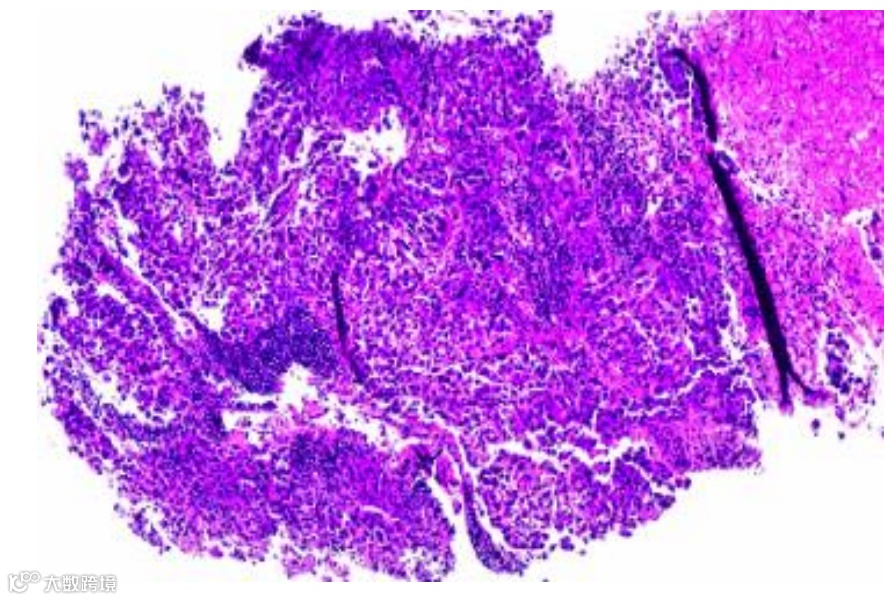

腹部CT显示肝脏肿块增大,淋巴结呈现弥漫性病变,并发现多处骨性病变。颈部超声检查发现右侧颈部淋巴结异常肿大,右侧甲状腺有一个5.3 cm大小的异质性肿块占位(图1),进行淋巴结活检,结果证实为转移性肝细胞癌(图2)。